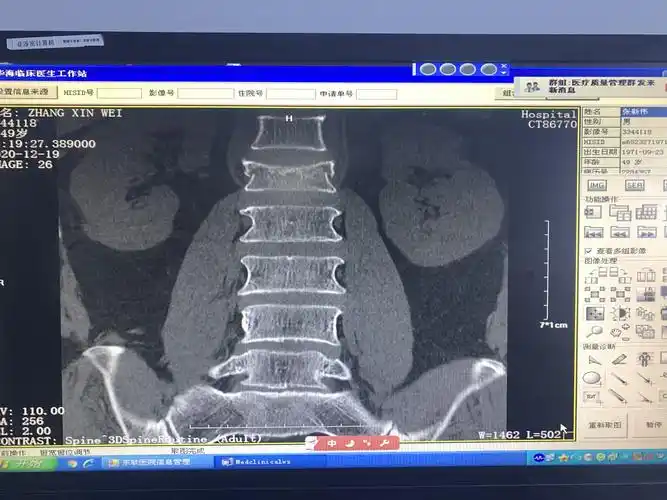

75岁腰椎压缩性骨折患者椎体成型手术一例